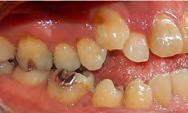

En la Figura 3 se muesta clase III molar y canina, el overjet y overbite negativos, en la Figura 4 las líneas medias coincidentes, la mordida abierta anterior, en la Figura 5 la clase III molar y canina, overjet y overbite negativos, en la figura 6 se ven formas de los arcos ovales, el apiñamiento severo superior e inferior.

Figura 3. Lateral derecha. Figura 4. Frente intraoral. Figura 5. Lateral izquierda. Figura 6. Intraorales oclusales.

En la radiografía lateral de cráneo tenemos (Figura 7) la clase III esquelética con un ANB de -1, hiperdivergencia, aumento de la altura facial inferior, proclinación de los incisivos superiores con 1 a plano palatino de 133°, línea roja sobre la longitud del incisivo superior.

En la radiografía panorámica (Figura 8) se observan 32 dientes presentes

en boca, con la rehabilitación de los órganos dentarios por oclusal, con obturaciones de amalgamas, e incrustaciones, y divergencias radiculares inadecuadas.

Figura 7. Radiografía lateral de cráneo. Figura 8. Radiografía panorámica.